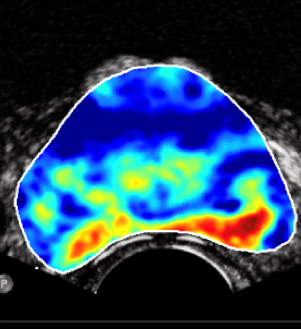

Start-up Angiogenesis Analytics, a spin-off of the Eindhoven University of Technology that currently works from the JADS Venture Campus in Den Bosch, is developing software that allows early detection of prostate cancer. It is a long term project: “Within four years it should be on the market”, says CEO and founder Mark Bloemendaal. “Precisely because it takes so long for the product to generate its own revenue, extra money is needed. The confidence of a bank then helps enormously when searching for investors.”

For ten years, TU Eindhoven has been researching ways to use ultrasound software to detect prostate cancer. In 2018, the university decided to translate the results into a spin-off. Last summer, Bloemendaal became involved in the medical software company. “I have been hired as director to clinically validate and market the software that has been developed. As an engineer, I have a lot of experience in this field. For example, I have been involved in the development of NightWatch, a clinically proven system that detects epileptic seizures.”

The fact that it takes another four years to get a product like PCaVision from an idea to a market product is not unusual in the medical world. The software is now being further developed into a usable solution in healthcare practice. This is followed by extensive clinical validation and certification. Bloemendaal is not afraid of the long term but he realizes that money is needed to bridge the period until there is real turnover. “Thanks to Rabobank’s commitment, I was able to convince other investors. We are now in the negotiation phase with a couple of big ones. This allows us to take the final steps, so that we can quickly build a product with which urologists can really get to work”.